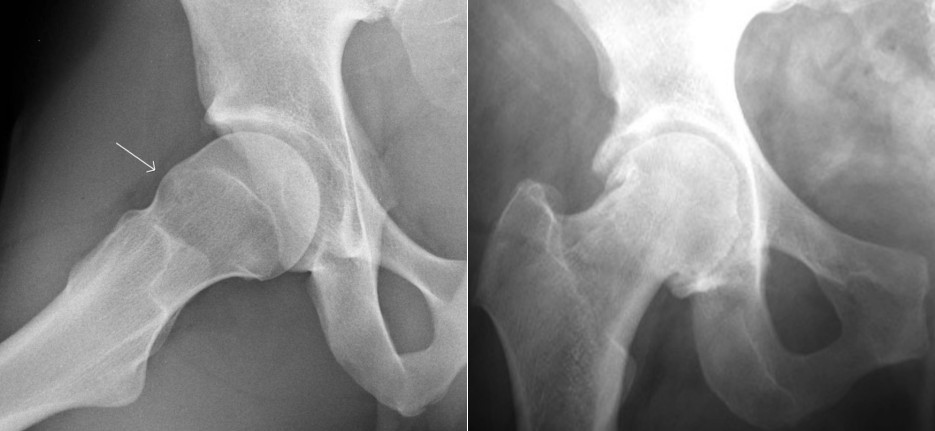

Displazija kolka je razvojna nepravilnost, pri kateri je acetabulum slabše razvit in nezadostno pokriva glavico stegnenice (slika 1).

Slika 1. Displazija kolka – rentgenska slika: ponvica sklepa je plitva in strma.

Acetabulum je strm in nezadostno pokriva glavico stegnenice, zato je obremenilna površina manjša, tlak v sklepu pa večji. Vrat stegnenice je nepravilne oblike (v valgusu).

Poleg tega sta lahko nepravilno razvita tudi glavica in vrat stegnenice. Zaradi manjše stične površine med glavico stegnenice in ponvico kolčnega sklepa ter posledično večjih tlakov med obremenjevanjem so mehka tkiva na robu sklepa, labrum in njemu priležni hrustanec, bolj obremenjena in se lahko s časom poškodujejo. Bolniki z nezdravljeno displazijo kolka imajo pomembno večje tveganje za nastanek zgodnje obrabe sklepa. Zakaj se pri nekaterih ljudeh razvije displazija kolka, pri drugih pa ne, ni povsem jasno. Večje tveganje predstavljajo prisotne razvojne nepravilnosti kolka pri bližnjih družinskih članih ter nekatere genetske in sistemske bolezni. Pri ženskah je displazija kolka trikrat pogostejša kot pri moških. Lahko se pojavi že ob rojstvu, pri otrocih, ki se porodijo z nogicami naprej (medenična vstava), ali če se plod razvija v maternici z manj plodovne tekočine ali v družbi dvojčka. Displazija kolka je lahko tudi posledica bolezni kolčnega sklepa v otroštvu, na primer Legg-Calve-Perthesove bolezni. Polovica bolnikov z displazijo ima slabo razvit tudi drugi kolk.